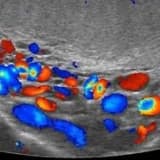

Çünkü meme kanserinin en erken bulgusu olan küçük küme mikrokalsifikasyon spiküle kitle ve kireçlenme odaklarını gösterebilen tek yöntem mammografidir. Meme kanserinin büyüyüp ele gelecek kadar kitle oluşturması ise bu aşamadan yıllar sonraya tekabül eder.